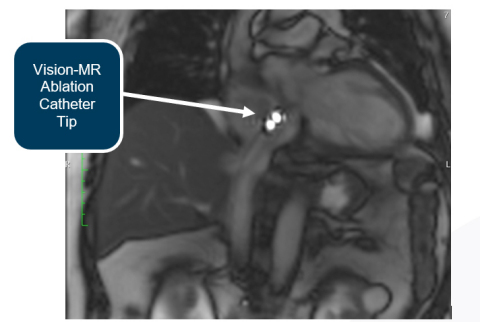

Es wurden Eingriffe mit nativer MRT-Bildgebung über den Siemens-Scanner durchgeführt, was das Unternehmen als Active Catheter Imaging bezeichnet. Mit dieser Bildgebungstechnik kann man den Ablationskatheter Vision-MR leicht erkennen, ohne dass aktives Tracking oder ein Kartierungssystem verwendet werden muss.

Active Catheter Imaging erwies sich bei den im Herzzentrum Dresden durchgeführten Eingriffen als äußerst effektiv. Dr. Christopher Piorkowski sagte dazu während eines Eingriffs: „Das ist sehr schön. Es ist besser als Fluoroskopie. Bei der Fluoroskopie kann man sich die Anatomie nur vorstellen. Hier kann man sie sehen.“